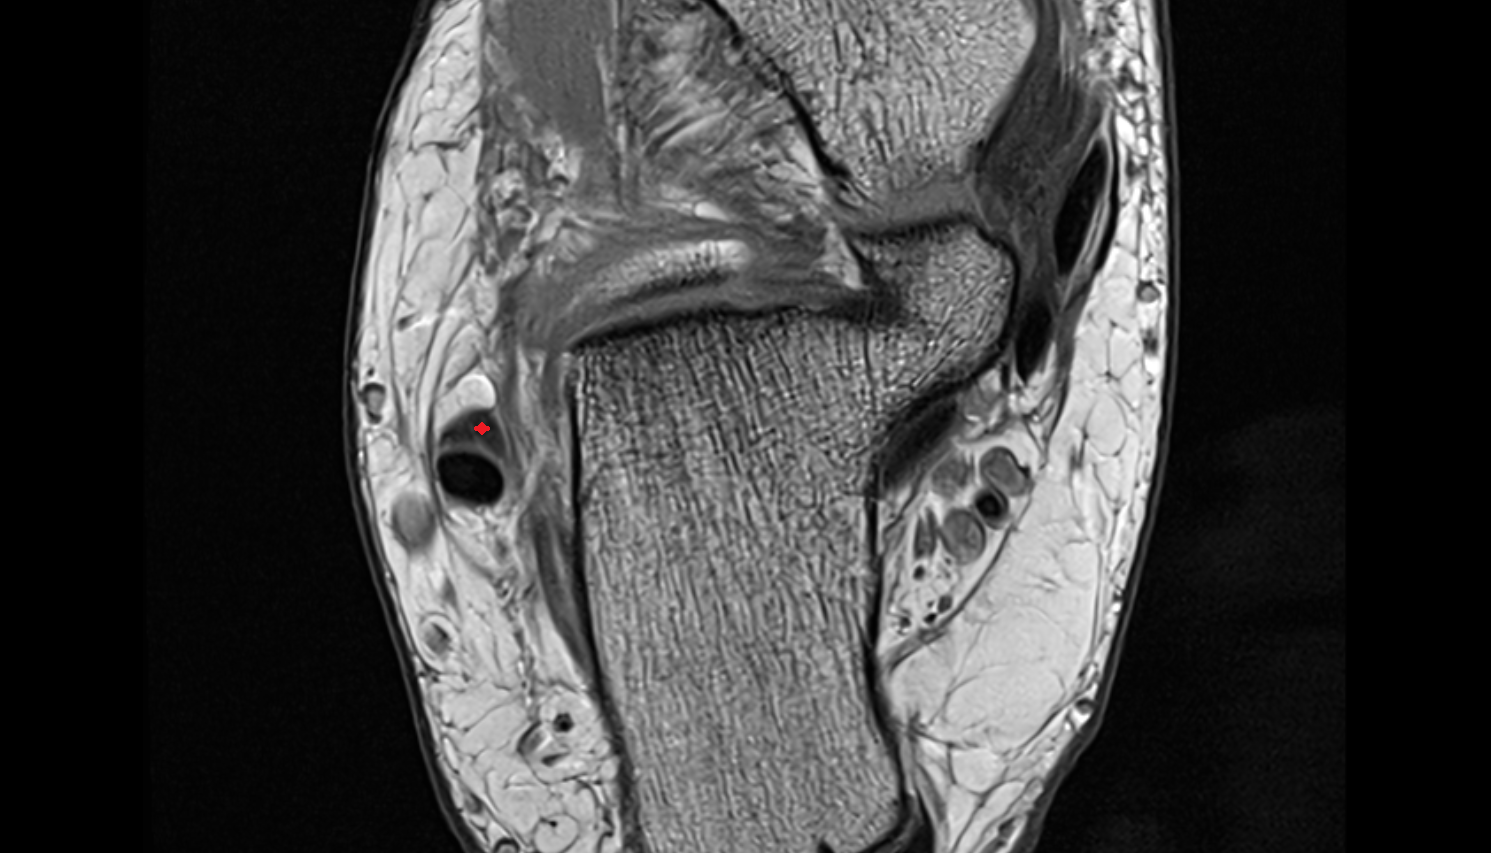

- Temporomandibular joint

- Mandibular condyle

- Mandibular fossa

- Articular disc of temporomandibular joint

- Articular eminence